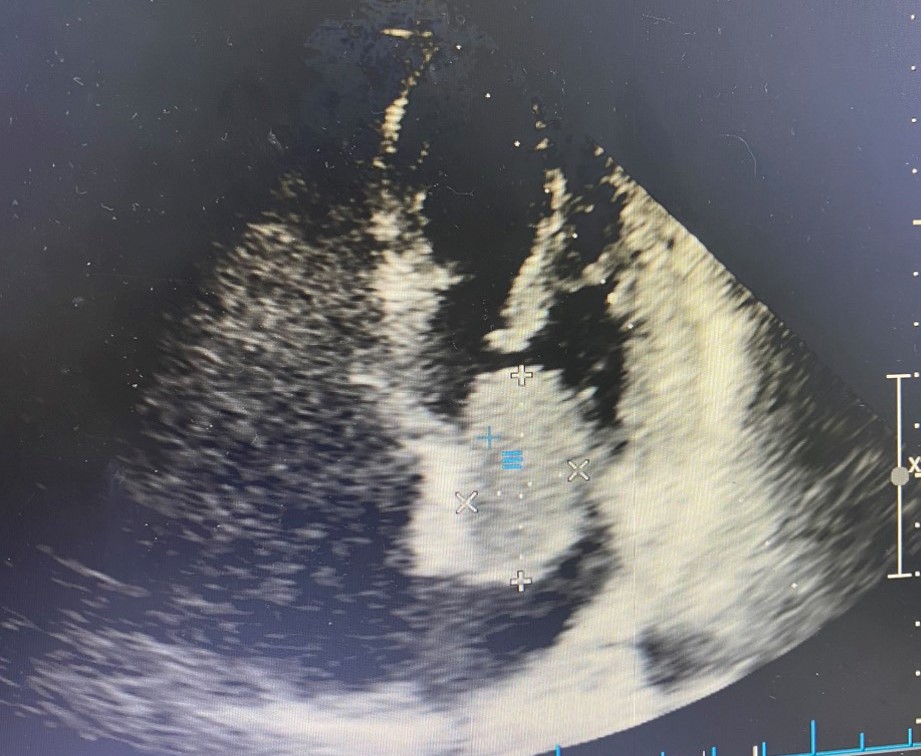

Bệnh nhân nữ 55 tuổi ở Đại Thắng, Tiên Lãng, Hải Phòng có tiền sử tăng huyết áp. Cách đây 2 tháng, người bệnh xuất hiện đau vùng lưng, đau tăng dần kèm tê bì vùng đùi phải. Ngày 16/5, người bệnh đến khám và được chẩn đoán thoát vị đĩa đệm L4,5, thoái hóa cột sống thắt lưng, có chỉ định phẫu thuật. Trước phẫu thuật, người bệnh được khám, đánh giá chuyên khoa tim mạch. Bất ngờ, hình ảnh siêu âm tim phát hiện bệnh nhân có khối u nhầy nhĩ trái kích thước lớn 3,8 x 2,7 cm dính vào vách liên nhĩ, di động làm hẹp một phần van hai lá trong thì tâm trương, nguy cơ ảnh hưởng đến huyết động cao.

- Hình ảnh u nhầy nhĩ trái qua siêu âm

Ở ca bệnh trên may mắn khối u chưa gây kẹt hay tắc van tim nên huyết động của bệnh nhân tạm ổn định. Tuy nhiên nếu kẹt sẽ gây tắc hoàn toàn van tim và gây đột tử cho người bệnh. Tại Bệnh viện đa khoa quốc tế Hải Phòng, bệnh nhân đã được chẩn đoán, phát hiện nhanh chóng và tư vấn, đánh giá để được phẫu thuật kịp thời.